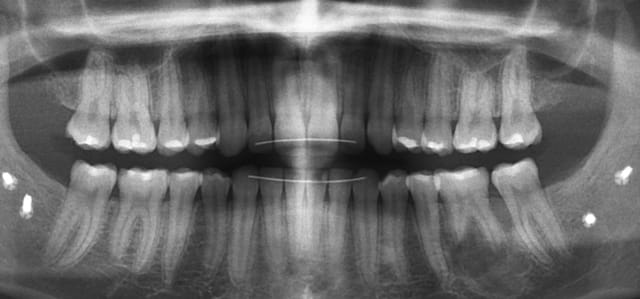

Sur la radio ci-jointe on note la présence d'une forme arrondie dont la situation correspond plus ou moins à la boule visible en bouche.

la radio montre des premo et molaires !

oui, ok, ce sont bien des molaires / prémolaires sur la radio, mais la 14 est couronnée, et a la place et la forme de la 13...

Plus bêtement récidive du kyste? (on a une image visible sur la radio) ou nécrose pulpaire 14? Dans les deux cas, ca serait plus cool...La biopsie doit être faite en effet.